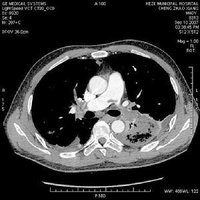

脂肪栓塞是由於循環血流中出現的脂滴阻塞於小血管所致,常見於長骨骨折,嚴重脂肪組織挫傷或脂肪肝擠壓傷時,脂肪細胞破裂,游離出的脂滴經破裂的小靜脈進入血流而引起脂肪栓塞,脂肪栓塞的後果取決於脂滴的大小和量的多少,以及全身受累的程度。脂肪栓塞主要影響肺和神經系統。循環血流中出現脂肪滴阻塞小血管,稱為脂肪栓塞(fat embolism)。脂肪栓塞的栓子常來源於長骨骨折、脂肪組織嚴重挫傷和燒傷,這些損傷可導致脂肪細胞破裂和釋出脂滴,由破裂的骨髓血管竇狀隙或靜脈進入血循環引起脂肪栓塞。脂肪肝時,由於上腹部猛烈擠壓、撞擊,使肝細胞破裂釋出脂滴進入血流。在非創傷性的疾病如糖尿病、酗酒和慢性胰腺炎血脂過高或精神受激烈刺激,過度緊張使呈懸乳狀態的血脂不能保持穩定而游離並互相融合形成脂肪滴。 創傷性脂肪栓塞時,脂肪栓子從靜脈入右心,再到達肺,直徑大於20mm的脂滴栓子引起肺動脈分支、小動脈或毛細血管的栓塞;直徑小於20mm的脂滴栓子可通過肺泡壁毛細血管經肺靜脈至左心達體循環的分支,引起全身多器官的栓塞,最常阻塞腦的血管,引起腦水腫和血管周圍點狀出血。少量脂肪栓塞組織和器官可無肉眼變化,僅在組織的冰凍切片脂肪染色時始見小血管腔內有脂滴。臨床表現上,在損傷後1~3天內出現突然發作性的呼吸急促,呼吸困難和心動過速。從脂滴釋出的游離脂肪酸還能引起局部中毒,損傷內皮細胞,出現特徵性的淤斑皮疹,也可能與血小板粘附在脂滴上,數量迅速減少有關。腦脂肪栓塞引起的神經症狀包括興奮、煩燥不安、譫妄和昏迷等。

脂肪栓塞的後果,取決於栓塞部位及脂滴數量的多少。少量脂滴入血,可被 巨噬細胞吞噬吸收,或由血中脂酶分解清除,無不良後果。若大量脂滴(9~20克)短期內進入肺循環,使75%的肺循環面積受阻時,可引起窒息和因 急性右心衰竭死亡。